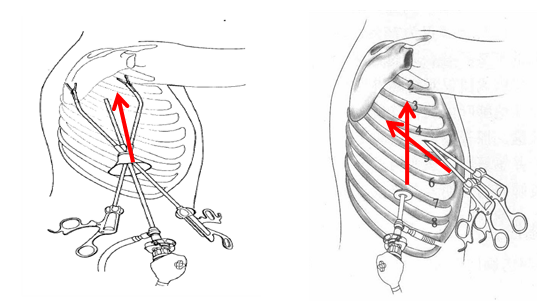

没想到我这么大岁数,切掉一个肺叶的十年后,再次做这么复杂的手术还这么顺利。 D大爷今年72岁,10年前曾行左肺上叶切除+淋巴结清扫术,手术标本病理为腺癌,术后给予了四次化疗。当时的胸部CT即可见右肺上叶小结节影,术后定期复查,病灶缓慢增大,一度略有缩小,此后再次逐渐增大。结合患者一直随访的影像学资料,杨如松院长考虑为右上肺新发恶性肿瘤。 2015年胸部CT 2020年胸部CT 虽然患者及其家属手术的意愿非常强烈,但此手术难度较高,原因在于: 1.患者年龄较高,手术风险大。 2.患者10 年前肺癌手术切除左边肺的一半,肺功能丧失较多。 3.病灶在右上肺的深部,切除有一定的难度。 为了保证患者术后的生活质量,我们不能够做肺的楔形切除这样的简单肺手术,而需要行肺段的切除。 EDDA重建提示病灶位置深 如果放在以前该患者就只能做做放化疗等保守治疗了。幸亏南京胸科医院目前引进了各种国内乃至国际上的先进技术。 如EDDA术前三D成像技术;只有单一3cm长切口的单孔胸腔镜技术;近红外荧光镜肺段、亚肺段精准定位技术等。 有了这些技术,杨如松院长心中有了底气。杨院长根据病人的情况设计手术方案,尽量减轻手术创伤,让接受第二次肺部复杂手术的高龄病人能够耐受,并且在术后能够顺利恢复。 根据术前EDDA三维重建,患者进行了单孔荧光胸腔镜S1a+2a切除术,术中先用ICG反染法确定段间面,再用膨胀萎陷法印证段间面,这保证了手术切除的精准性。 患者术中快速病理为贴壁型腺癌,这也印证了杨如松院长术前对患者肺结节良恶性的判断。 术后5天,D大爷非常顺利的出院了。出院前开心的窦大爷连声感谢杨如松院长:没想到我这么大岁数,切掉一个肺叶的十年后,再次做这么复杂的手术还这么顺利,谢谢、谢谢! 基本情况

手术方案